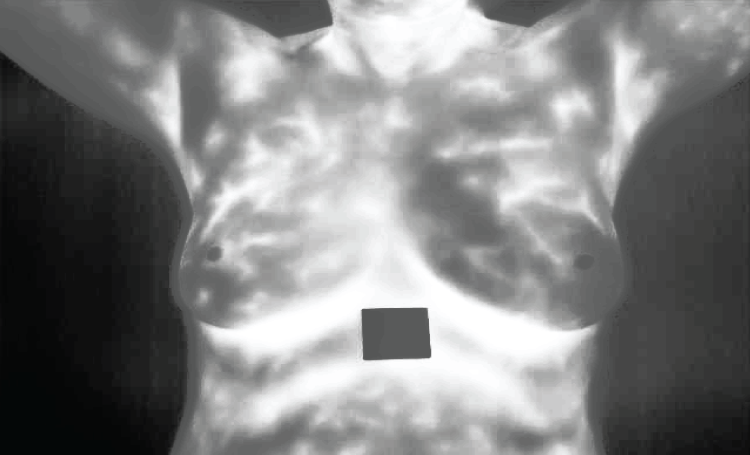

The picture labeled Fig. 9 presents an increased image subjected to contrast-limited adaptive histogram equalization (CLAHE). This move enhances the contrast of the image, making more visible the essential features without exaggerating noise. Increased contrast is important in distinguishing between normal and abnormal patterns and for accurate feature extraction as well.

Figure 9: Enhanced image

Fig. 10 shows what happens when bilateral filtering is applied to this enhanced picture. Bilateral filtering reduces noise while preserving edges related to significant anatomical structures on images. This nonlinear filter technique is useful in eliminating noise by combining both spatial closeness and resemblance in pixel values thereby ensuring that crucial anatomical details are not damaged.

Figure 10: Resultant of Bilateral filtering

In Fig. 11, the result obtained is after applying Non-Local Means (NLMS) filter on the image which comes from previous step. The filter considers a wider region when averaging pixels than simple local methods do by considering their likeness with targeted one over larger area from other parts of an image (e.g., cancerous regions).

Figure 11: Resultant of NLMS filter